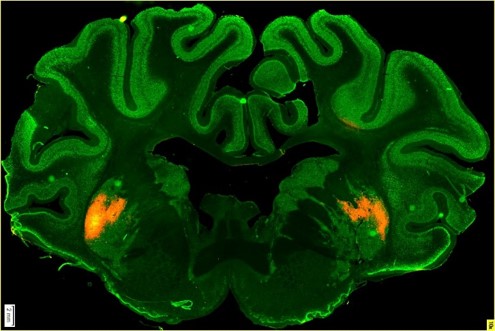

Používali k tomu jako vektor adeno-asociovaný virus. Na prasatech jsme ale nejdřív museli ověřit biodistribuci přípravku. Aplikovali jsme tedy virový vektor s fluorescenční svíticí značkou, abychom pak v mozku viděli, kam se virus dostal. V roce 2015 jsme začali pracovat na prvních studiích.

Kolega Štefan Juhás aplikoval virus s fluorescenčním proteinem prasátkům do mozku, konkrétně do oblasti striata v bazálních gangliích, která jsou odpovědná za koordinaci pohybu. Pak jsme prasata utratili a pozorovali mozkové řezy, abychom viděli, kam všude se virus se značkou rozšířil. Rozšířil se velmi dobře, aniž by došlo k poškození buněk, jenom k mírnému zánětu vlivem fluorescenční značky.